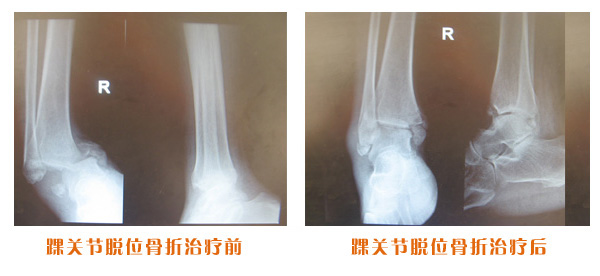

踝關節脫位骨折治療前后對比